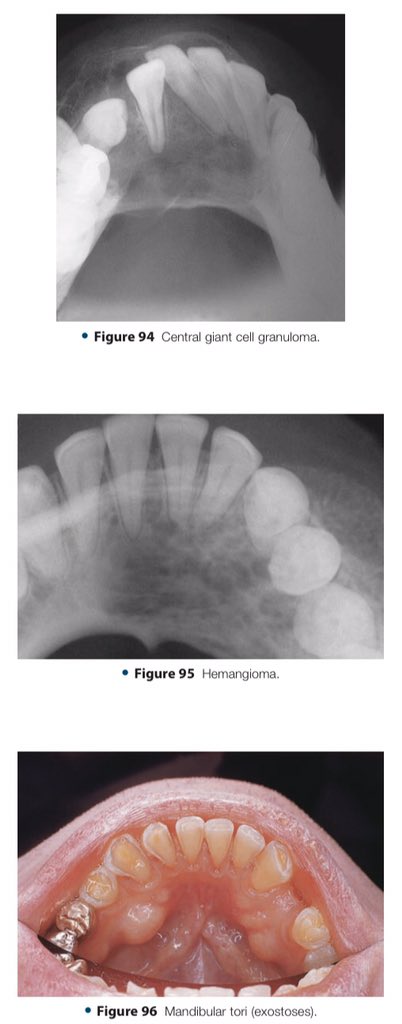

🔍| Differential Diagnosis Approach to Jaw Lesions. #aboutDent